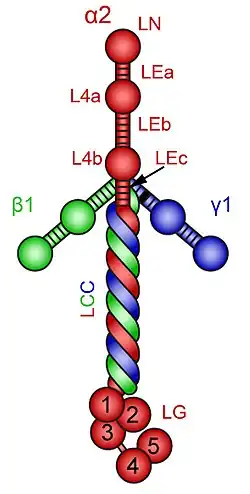

| Diagrammatic illustration of laminin-211 or Laminin-alpha2 chain. The alpha2 chain is shown in red. | |

Cause

There is no definite cure available for LAMA2-MD. However, preclinical studies on experimental animal models of Laminin alpha-2 chain deficient congenital muscular dystrophy are showing favorable yet early results. Generally, these preclinical studies are geared toward investigating the various factors behind disease initiation and progression, and exploration of potential ameliorating or curative therapies.[24] Preclinical studies focus on combating substances that regulate and promote muscle fibrosis in the pathogenesis of LAMA2-MD e.g., TGF-β. This may reduce muscle fibrosis and enhance healthy muscle architecture subsequently.[25][26][27] Alternatively, preclinical studies can be geared toward enhancing proteins that are involved in muscle regeneration. Laminin alpha2 (Laminin-211) and laminin-221 complex are an important molecule for muscle cell receptors namely integrin-α7β1 and α-dystroglycan. In LAMA2-CMD the laminin alpha2 deficiency results in malfunctioning or down regulation of integrin-α7β1 and α-dystroglycan. This disrupts the proper linkage between the basal lamina and muscle cell membrane. Consequently, the contractile mechanism is disrupted. Integrin-α7β1 is important to satellite cell function, and myoblast adhesion and viability. Thusly, integrin-α7β1is an important contributor to skeletal muscle regeneration. Cell therapies that compensate for the deficiency or down regulation of integrin-α7β1 have the potential to delay or control the muscle degenerative process and preserve muscle architecture in LAMA2-CMD patients. Additionally, the use of laminin-111 treatment in experimental mouse models of LAMA2-CMD has showed satisfactory results in terms of increase in life expectancy muscle function and regeneration.[28]